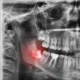

ฟันลักษณะไหน ควรจัดฟัน EF Line

การจัดฟัน EF Line เป็นการจัดฟันที่มีเครื่องมือการจัดฟันเป็นลักษณะชิ้นยางที่มีหลากหลายสี ซึ่งใช้ในการปรับโครงสร้างใบหน้าของเด็ก ปรับตำแหน่งลิ้น ปรับรูปของขากรรไกร ซึ่งลักษณะของเด็กที่ควรเข้ารับการจัดฟัน EF Line ก็คือ เด็กที่มีลักษณะฟันยื่น เด็กที่ฟันล่างคร่อมฟันบน …